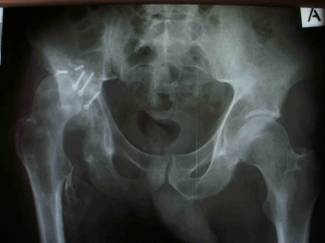

operation day. The patient came again to the hospital three

months after the surgery at the emergency department with loss

of fixation and the hip dislocated posteriorly again. [fig.3] As

Fig.3: AP radiograph showing a loss of reduction and

reconstruction failure of the right hip.